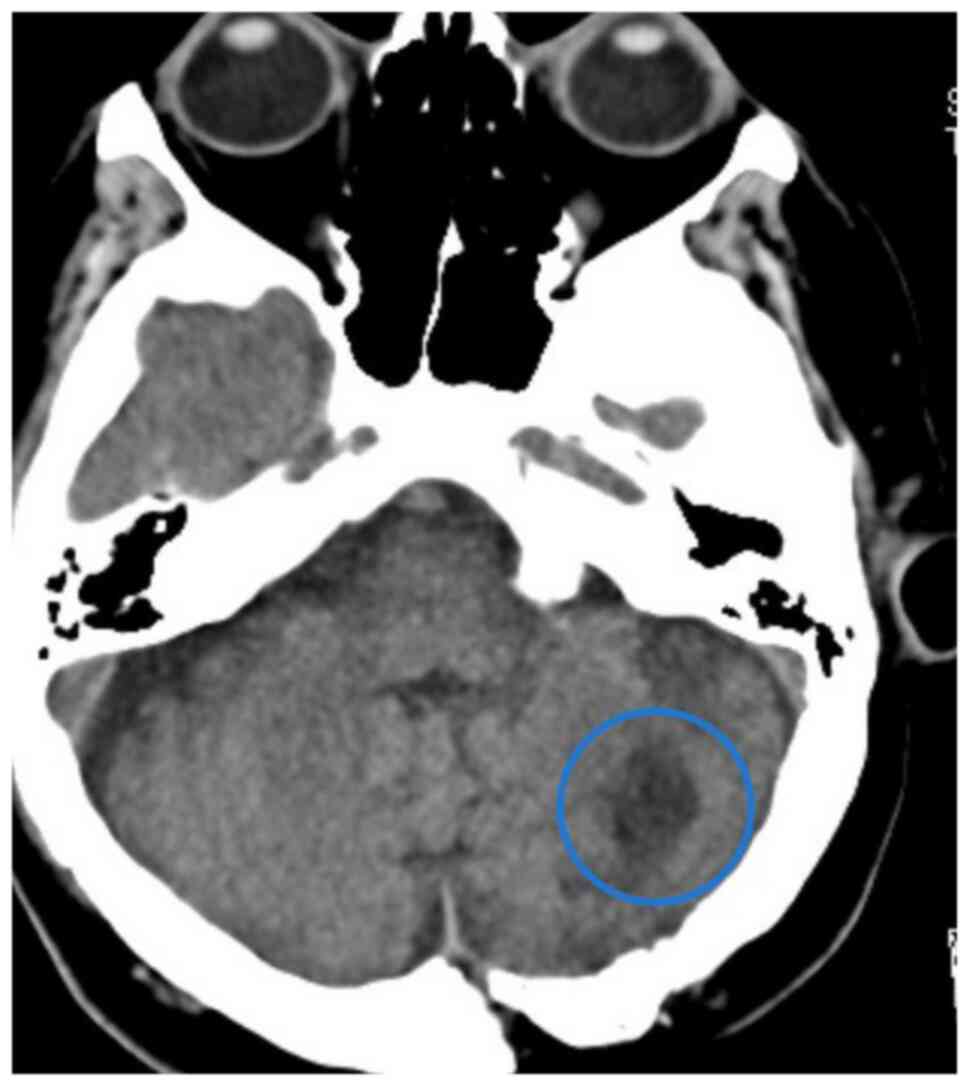

In February 2023, cranial CT revealed a 21-mm iso-hyperdense mass accompanied by edema extending to the fourth ventricle and right cerebellum (Fig. 3). Pathological examination of the excised cranial lesion confirmed melanoma metastasis (Fig. S3). The patient subsequently received postoperative cranial radiotherapy (10 days, 30 Gy). In April 2023, a lesion causing small bowel obstruction was resected following abdominal CT performed due to symptoms associated with ileus (absent gas and stool passage); evaluation for ileus and the pathological result were consistent with malignant melanoma metastasis. In addition, irregularly circumscribed hypodense areas, the largest measuring 36×30 mm in segment 7 of the liver, were detected. A biopsy of the suspected metastatic liver lesion confirmed malignant melanoma metastasis. Disease progression (including new metastatic solid nodules detected in both lungs) was observed in PET-CT scans and dacarbazine treatment was initiated in July 2023.

Brain metastasis: A 21-mm-sized,

iso-hyperdense mass with associated edema extending to the fourth

ventricle and right cerebellum in the cranium was observed on CT

imaging (blue circle; March 2023).

Figure 3.

Brain metastasis: A 21-mm-sized, iso-hyperdense mass with associated edema extending to the fourth ventricle and right cerebellum in the cranium was observed on CT imaging (blue circle; March 2023).